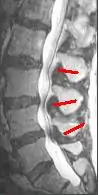

Since an MRI provides excellent imaging of blood vessels and tissues, it is recognized as the best type of imaging to observe signs associated with lumbar compression. The precise measurement of the diameter of the spinal canal is a particularly important component when determining the severity of the stenosis itself.[2] High strength 3-Tesla MRI machines are being utilized due to the increased vascular imaging capabilities. Better resolution capacity allows for more detailed observations by the healthcare provider. The sharp contrast of the high power MRI outlines details in the vertebra that are critical when examining a patient with lumbar spinal stenosis who may need a laminotomy.[1] MRI scanning post invasive surgery is used to see the quality of the surgery itself, yet the appropriate postoperative time elapsed before conducting an MRI is a debated topic.[2]